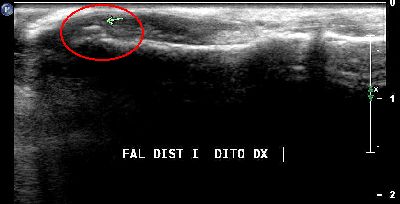

Microavulsione falange distale primo dito (img. 01) microavulsione falange distale primo dito 01